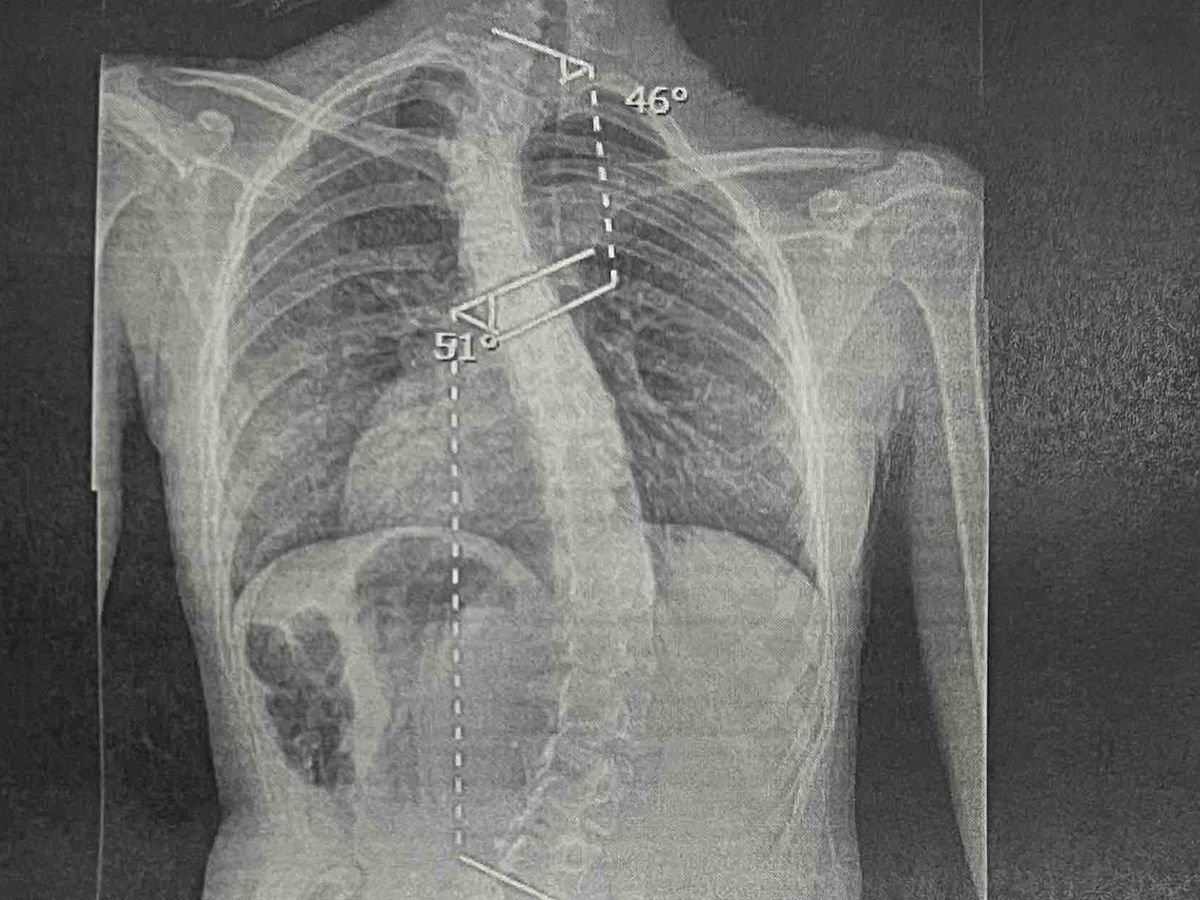

We knew she had mild scoliosis which was being monitored by her doctor at every yearly visit. This year we went to a different provider, who then sent us to a specialist, who confirmed Bella had what is called a butterfly vertebrae which is a rare congenital anomaly of the spine that can occur in the neck as well as 45 degree curvature which she couldn't guarantee that it wouldn't progress as the years went by, so surgery is her best option. We were unaware that scoliosis affects heart, lungs, and digestive system. This explains so much since we have been referred and seen by two heart specialists that said the heart murmur is so small they weren't worried about it, but those digestive issues continue being a problem.